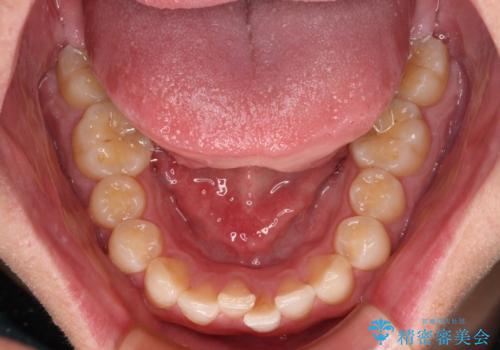

シザーズバイトの奥歯も正常なかみ合わせに改善

捻転歯も回転が修正され、全体的に清掃性・咀嚼効率が向上